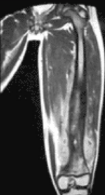

Thigh Rhabdmiosarcoma